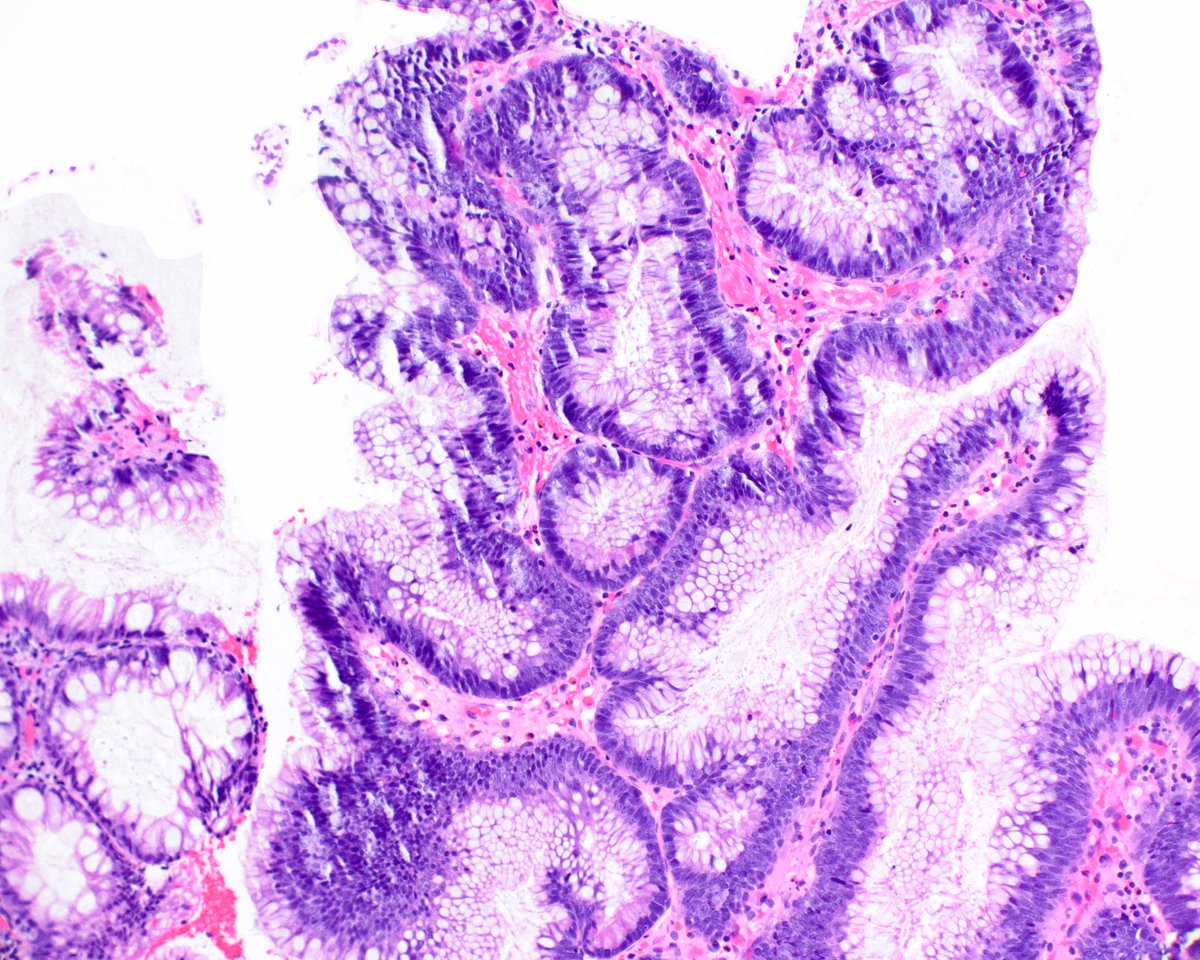

75-year-old male with a 4 cm mass in the lower pole of the right kidney. CA9 diffusely positive = CCRCC with a cute morphological appearance. #gupath GU Pathology Society (GUPS) International Society of Urological Pathology